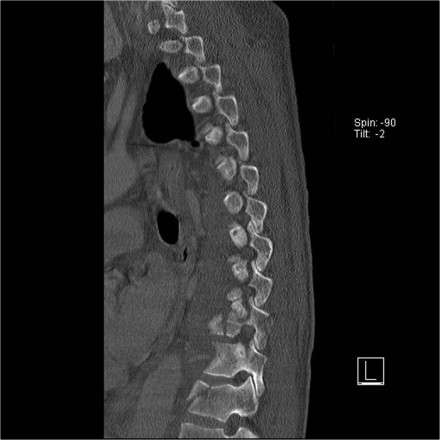

Here is a patient with distraction on the anterior side.

Notice the rigid spine and how easily this major injury can be overlooked.

This patient had a motorcycle accident.

The MRI demonstrates rupture of the flava ligaments, interspinous and supraspinous ligaments as well as fracture of the posterior elements and compression of the vertebral body.

A posterior spondylodesis was performed.